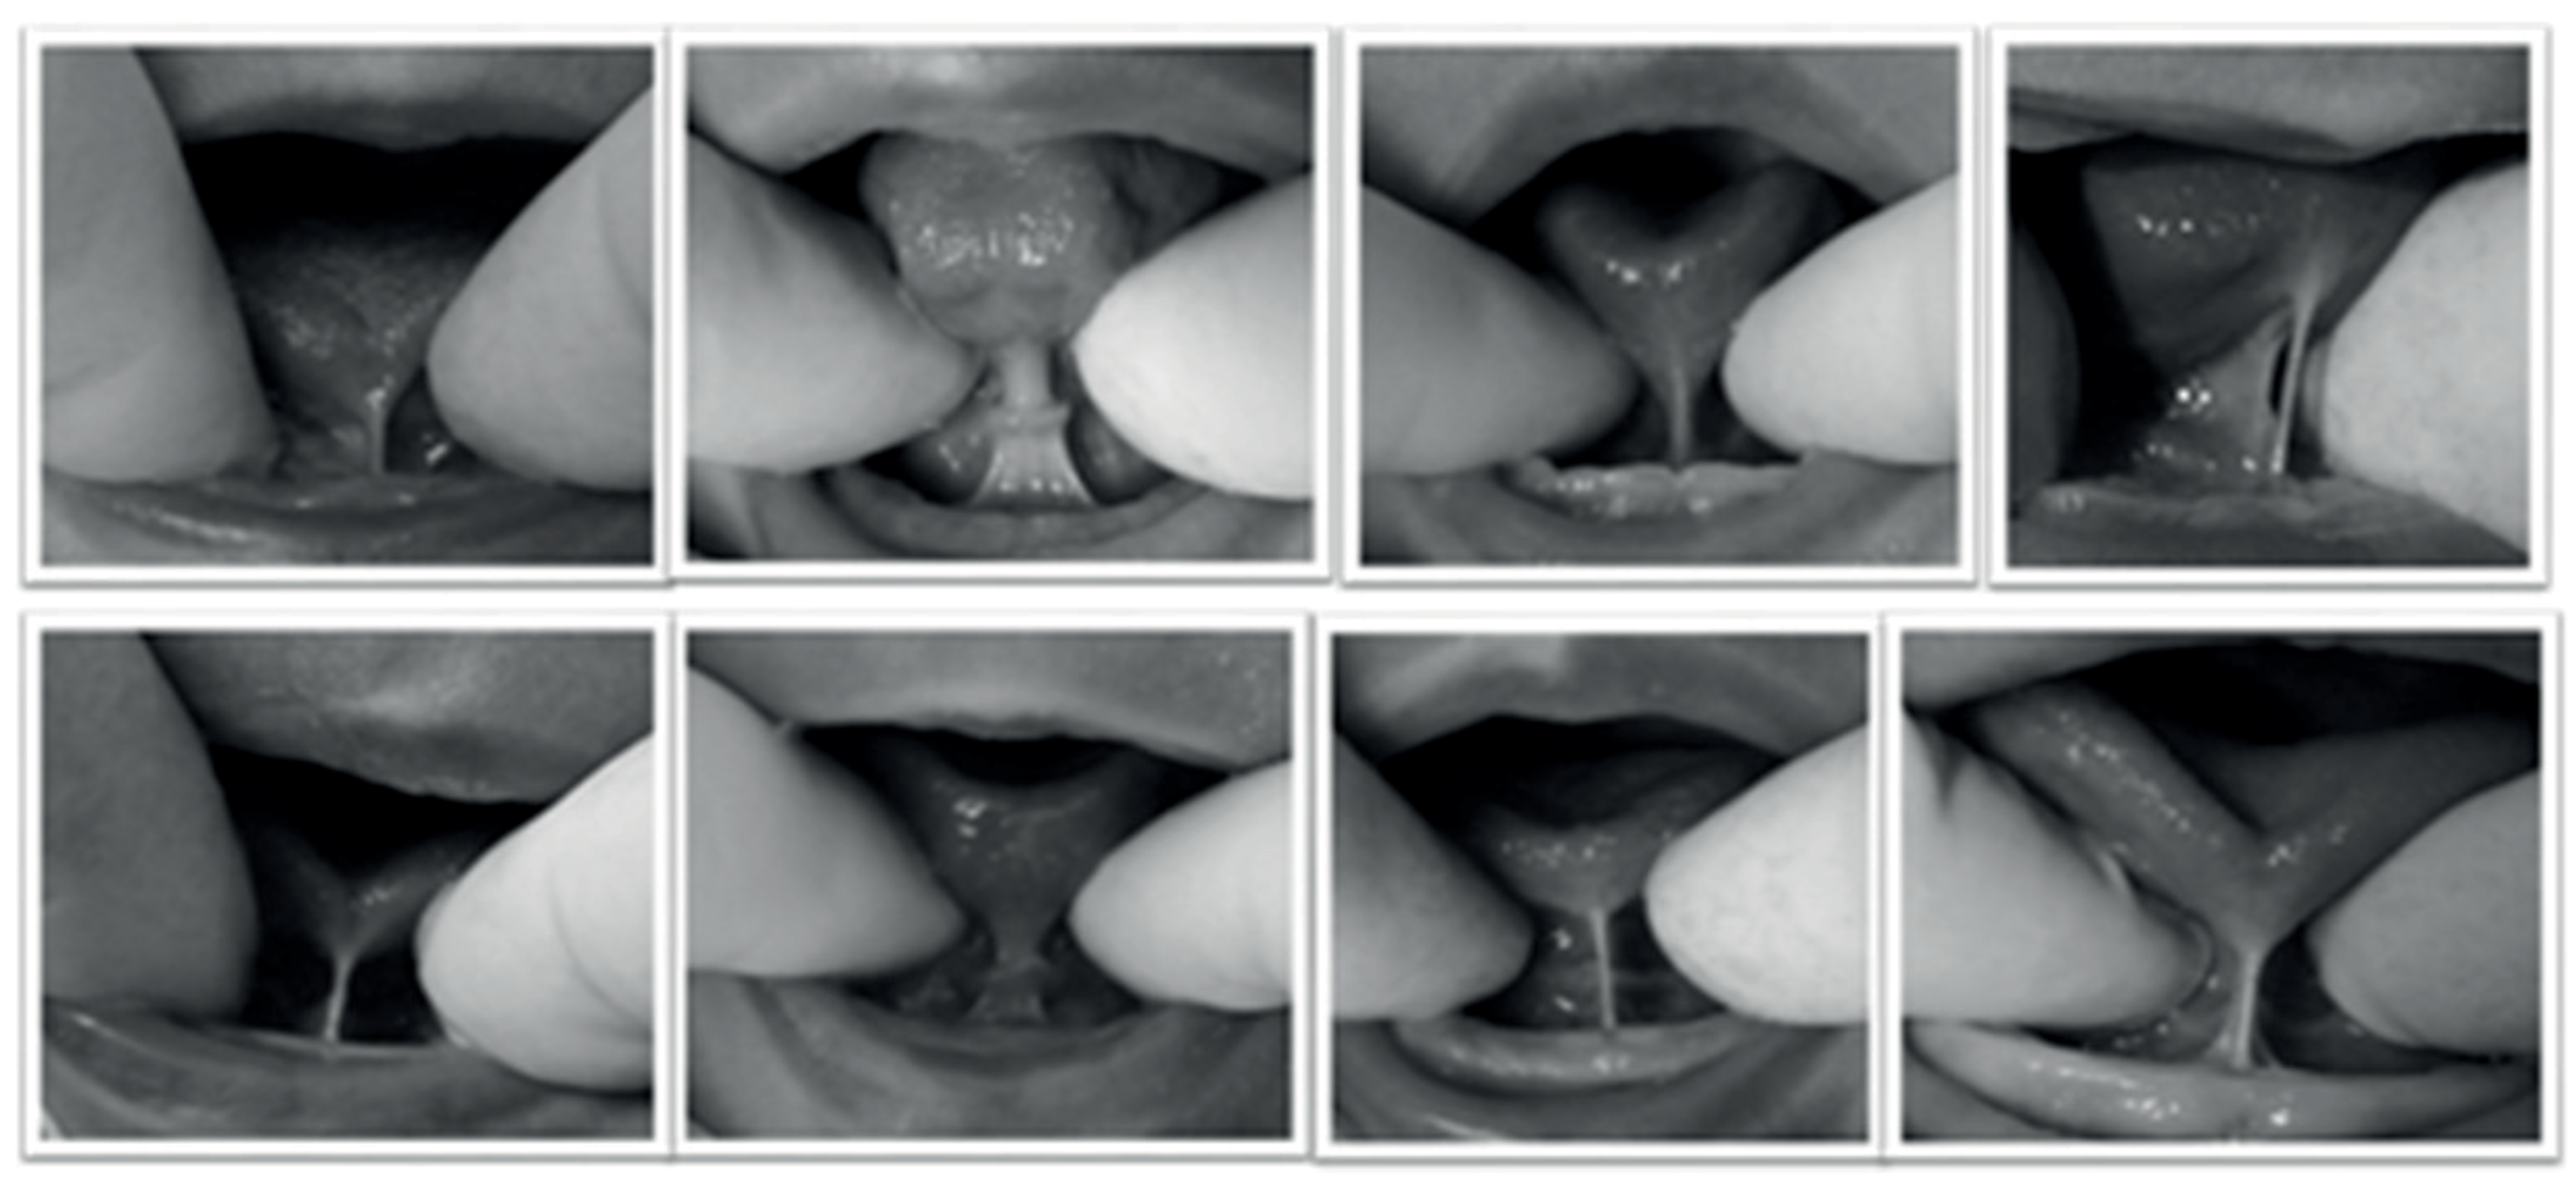

Lingual frenulum with mucosal hooding classified as posterior.

For the anatomical-functional evaluation, the Speech Language Pathologist opened the infant’s mouth by pushing down the infant’s chin with the thumbs, and at the same time, elevated the tongue using the index fingers. The maneuver enabled the clinician to have complete visualization of the infant’s lingual frenulum. Lingual frenulum with mucosal hooding was classified as posterior (Figure 1). For the evaluation of the nutritive and non-nutritive sucking, tongue movements, sucking rhythm, coordination among sucking/swallowing/ breathing, nipple chewing, and clicking during sucking were assessed.